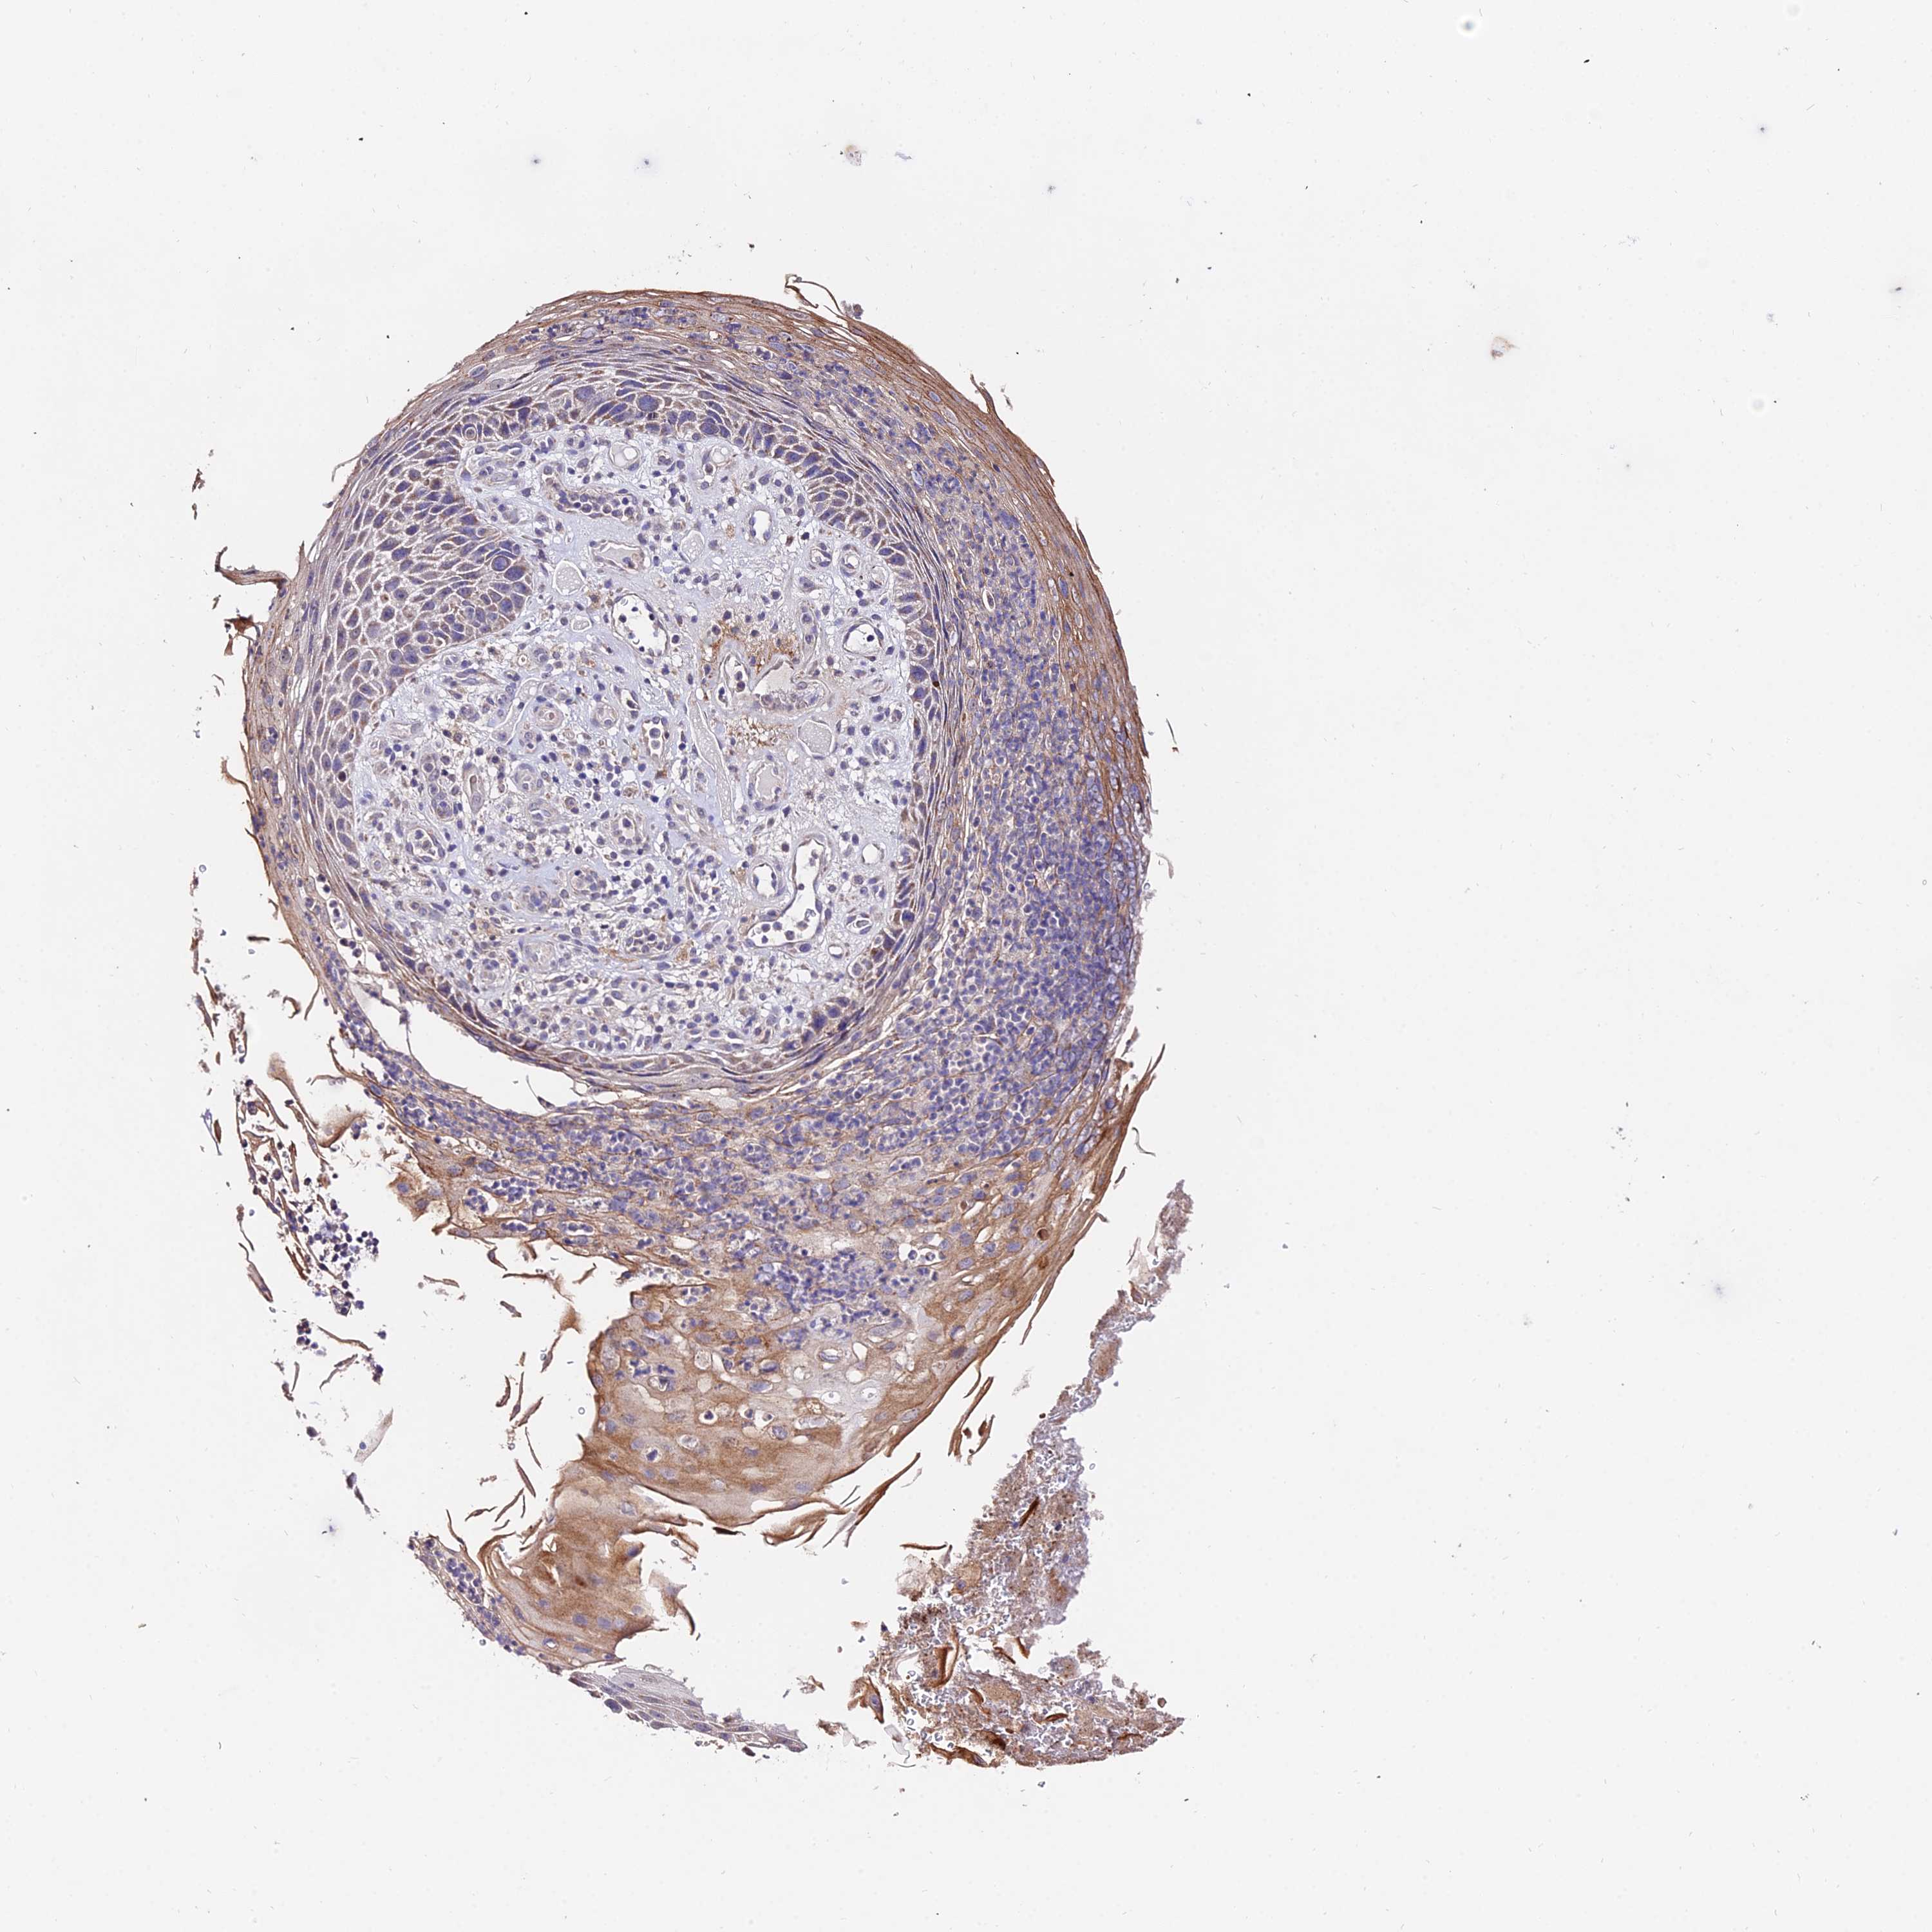

SKIN CANCER - Protein expressioni

A mouse-over function shows sample information and annotation data. Click on an image to view it in a full screen mode. Samples can be filtered based on level of antibody staining by selecting one or several of the following categories: high, medium, low and not detected. The assay and annotation is described here.

Antibody stainingi

Antibody staining in the annotated cell types in the current human tissue is reported as not detected, low, medium, or high, based on conventional immunohistochemistry profiling in selected tissues. This score is based on the combination of the staining intensity and fraction of stained cells.

Each image is clickable and will lead to virtual microscopy that enables deeper exploration of all samples and also displays staining intensity scores, fraction scores and subcellular localization as well as patient and tissue information for each sample.

Antibody HPA042994

Staining

High

Medium

Low

Not detected

Intensity

Strong

Moderate

Weak

Negative

Quantity

>75%

75%-25%

<25%

None

Location

Nuclear

Cytoplasmic/membranous

Cytoplasmic/membranous,nuclear

Basal cell carcinoma

Squamous cell carcinoma, NOS

Squamous cell carcinoma, metastatic, NOS